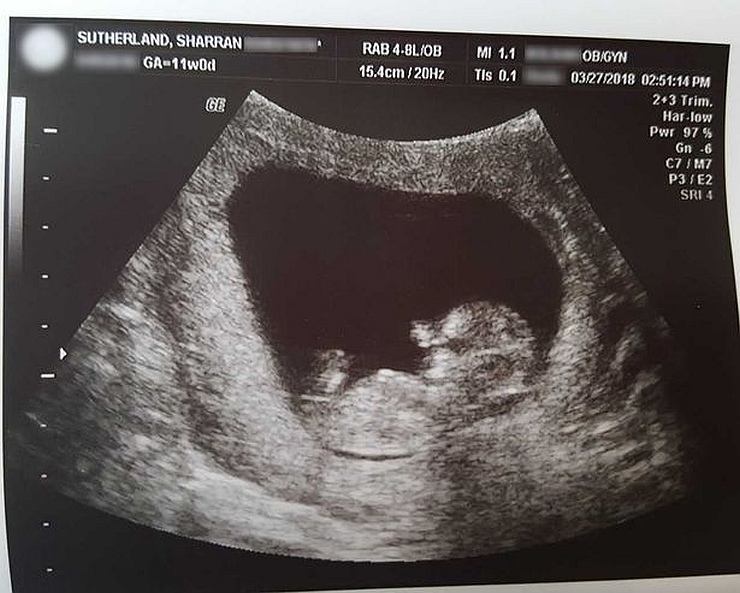

SLIKA: Miran na ultrazvuku - Foto: Sharran Sutherland

Sharran Sutherland, koja živi u Fair Groveu u Missouriju (SAD), sa četrdeset godina je izgubila svog sina Mirana u 14. tjednu trudnoće. Ultrazvuk je pokazao da je malenome srce prestalo kucati.